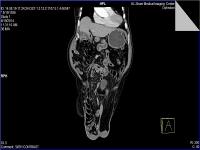

Medical imaging is an important investigative tool will help doctors to reach for the diagnosis of certain diseases, and the the advanced and high-quality imaging technologies are an important factor in maintaining the health of patients and accurate diagnosis of pathological lesions.